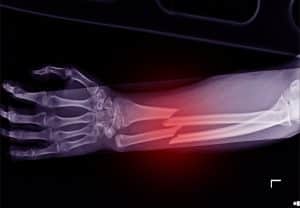

A typical fracture (such a minor break of your arm when you fall from a tree as a kid) usually only requires to be set and held into place by a cast, but more serious breaks may need surgical intervention. Internal fixation is a type of surgical procedure that involves repositioning bone fragments and securing them with implants like plates, screws, nails, and wires. This technique not only facilitates shorter hospital stays but also promotes an earlier return to function, while decreasing the risk of improper healing or healing in the wrong position of fractured bones.

It depends on the severity and type of bone break. The type of break is classified by pattern, cause, and body part. With more serious bone breaks, surgical interventions such as internal fixation may be necessary.

- Transverse fracture. These fractures occur when the break runs horizontally across the bone, perpendicular to its natural direction. Often referred to as complete fractures, this implies that the fracture line extends entirely through the bone. Typically affecting long bones in the body, transverse fractures represent a specific pattern of breakage. These are most commonly seen after car accidents, and while they do not always require surgery, more severe cases may.